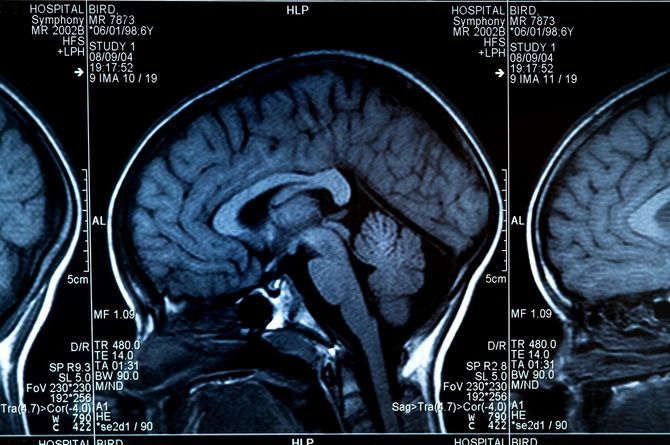

創造性がなくなるので、アイデアも出てこなくなり、考え方も平板になります。実際に症状は様々な形で現れてくるのですが、前頭葉の老化を示す萎縮の様子は、MRIなどの画像でははっきりと見てとれるにもかかわらず、本人はなかなかその症状に気づかないという厄介さがあります。